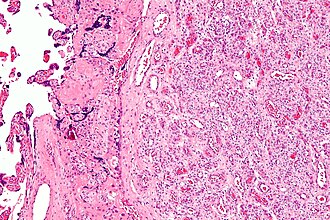

Chorangioma. H&E stain. | |

| LM | abundant capillaries surrounded by stroma |

| LM DDx | chorangiosis, chorangiomatosis |

Microscopic

Features:[1]

- Mass of capillaries - key feature.

- +/-High cellularity.

- +/-Degenerative changes.

- Must be differentiated from chorangiomatosis (associated with preeclampsia & IUGR) and chorangiosis (associated with maternal diabetes mellitus).[1]